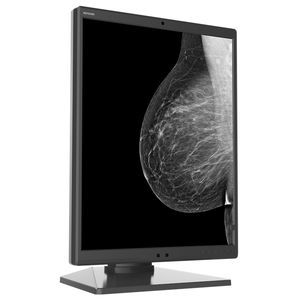

- Monitor de diagnóstico

- Nanjing Jusha Display Technology

Monitor médico CR240Gde diagnósticode alta definición1920x1200

Descripción

Las pantallas profesionales de Jusha Médico cuentan con alta resolución, alto brillo y escala de grises de 16 bits (65536 niveles), con LUT incorporado de estándar DICOM, y puede satisfacer los altos requisitos de diagnóstico clínico de sistema radiológico como PACS, mamografía, CR, DR.

1. Alto brillo

La pantalla tiene un brillo calibrado máximo de hasta 2500cd/m2. Ofrece mejor profundidad de imágenes atravesando la combinación del brillo y ratio de contraste , así facilita localizar las enfermedades.